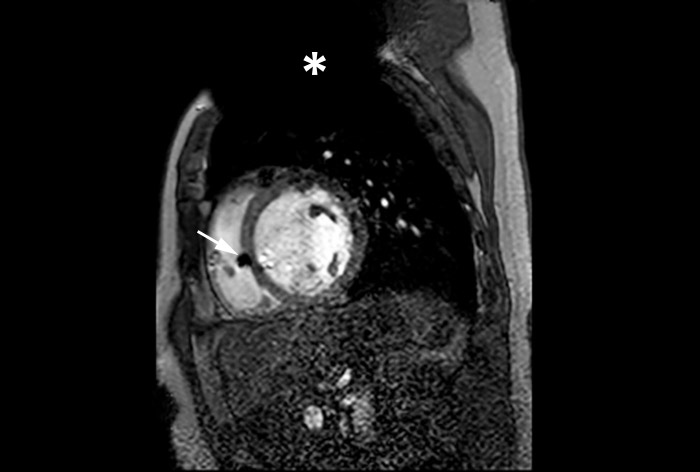

MR Conditional ICD

MRI of heart with MR Conditional ICD

A patient with an MR Conditional ICD and suspected myocarditis presented for MRI. This short axis view of the heart is created with an SSFP (steady state free precession) sequence on a Philips Achieva 1.5T system. The cardiac MRI exam reveals normal dimensions and regular function of the right and left ventricle. Note the ICD lead in the right ventricle (arrow) and the signal void in the left pectoral region, indicating the ICD-IPG (asterisk). Courtesy of Dr. Sommer.